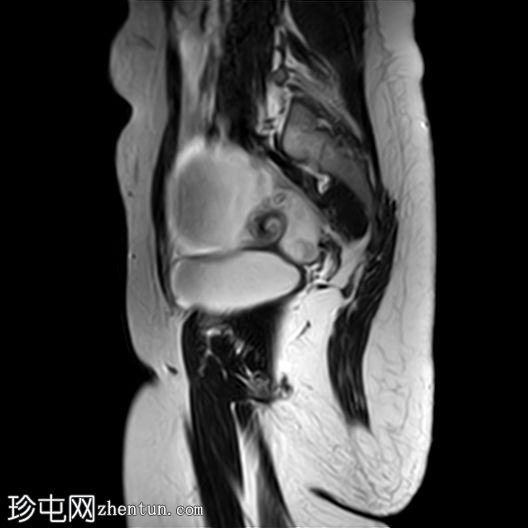

矢状位

T2加权像

右侧卵巢增大,卵泡呈周边排列。

附件血管蒂扭转(漩涡征)。

右侧附件旁可见一较大的、边界清晰的盆腔囊性病变,向右倾斜,提示为卵巢旁囊肿。

本病例展示了卵巢扭转的典型影像学特征,包括卵巢增大、卵泡呈周边移位、卵巢向内侧偏移以及特征性的漩涡征。

在这种情况下,较大的卵巢旁囊肿被认为是发生卵巢扭转的高危因素。如果卵巢旁囊肿较大(>5厘米)或活动度较大,其重量/活动度增加会牵拉附件,导致卵巢和输卵管发生扭转。